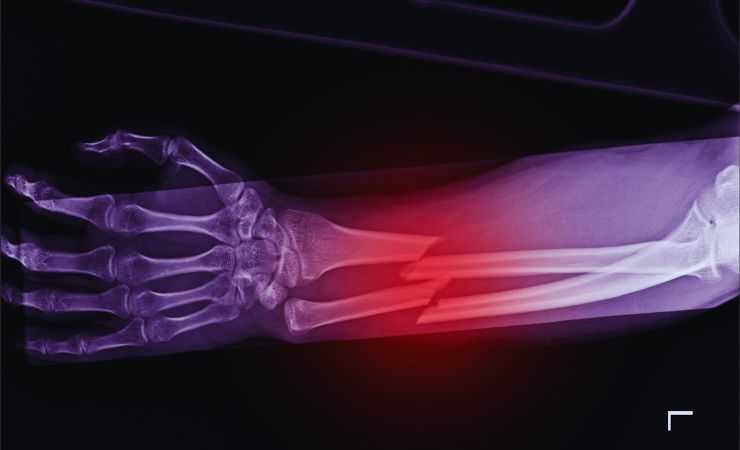

Las fracturas óseas representan uno de los desafíos más comunes en la práctica ortopédica y traumatológica. Su manejo, seguimiento y rehabilitación exigen herramientas diagnósticas precisas y seguras.

Tradicionalmente, las fracturas se siguen mediante radiografías convencionales, tomografías computarizadas o estudios con densitometría ósea como la DXA (absorciometría dual de rayos X). Si bien estos métodos son convencionales y bien establecidos, conllevan exposición a radiación. La repetición frecuente de esos exámenes aumenta la dosis acumulativa para el paciente, lo que puede ser especialmente problemático en niños, ancianos o quienes requieren un seguimiento prolongado.